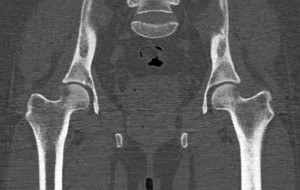

Тазобедренные суставы